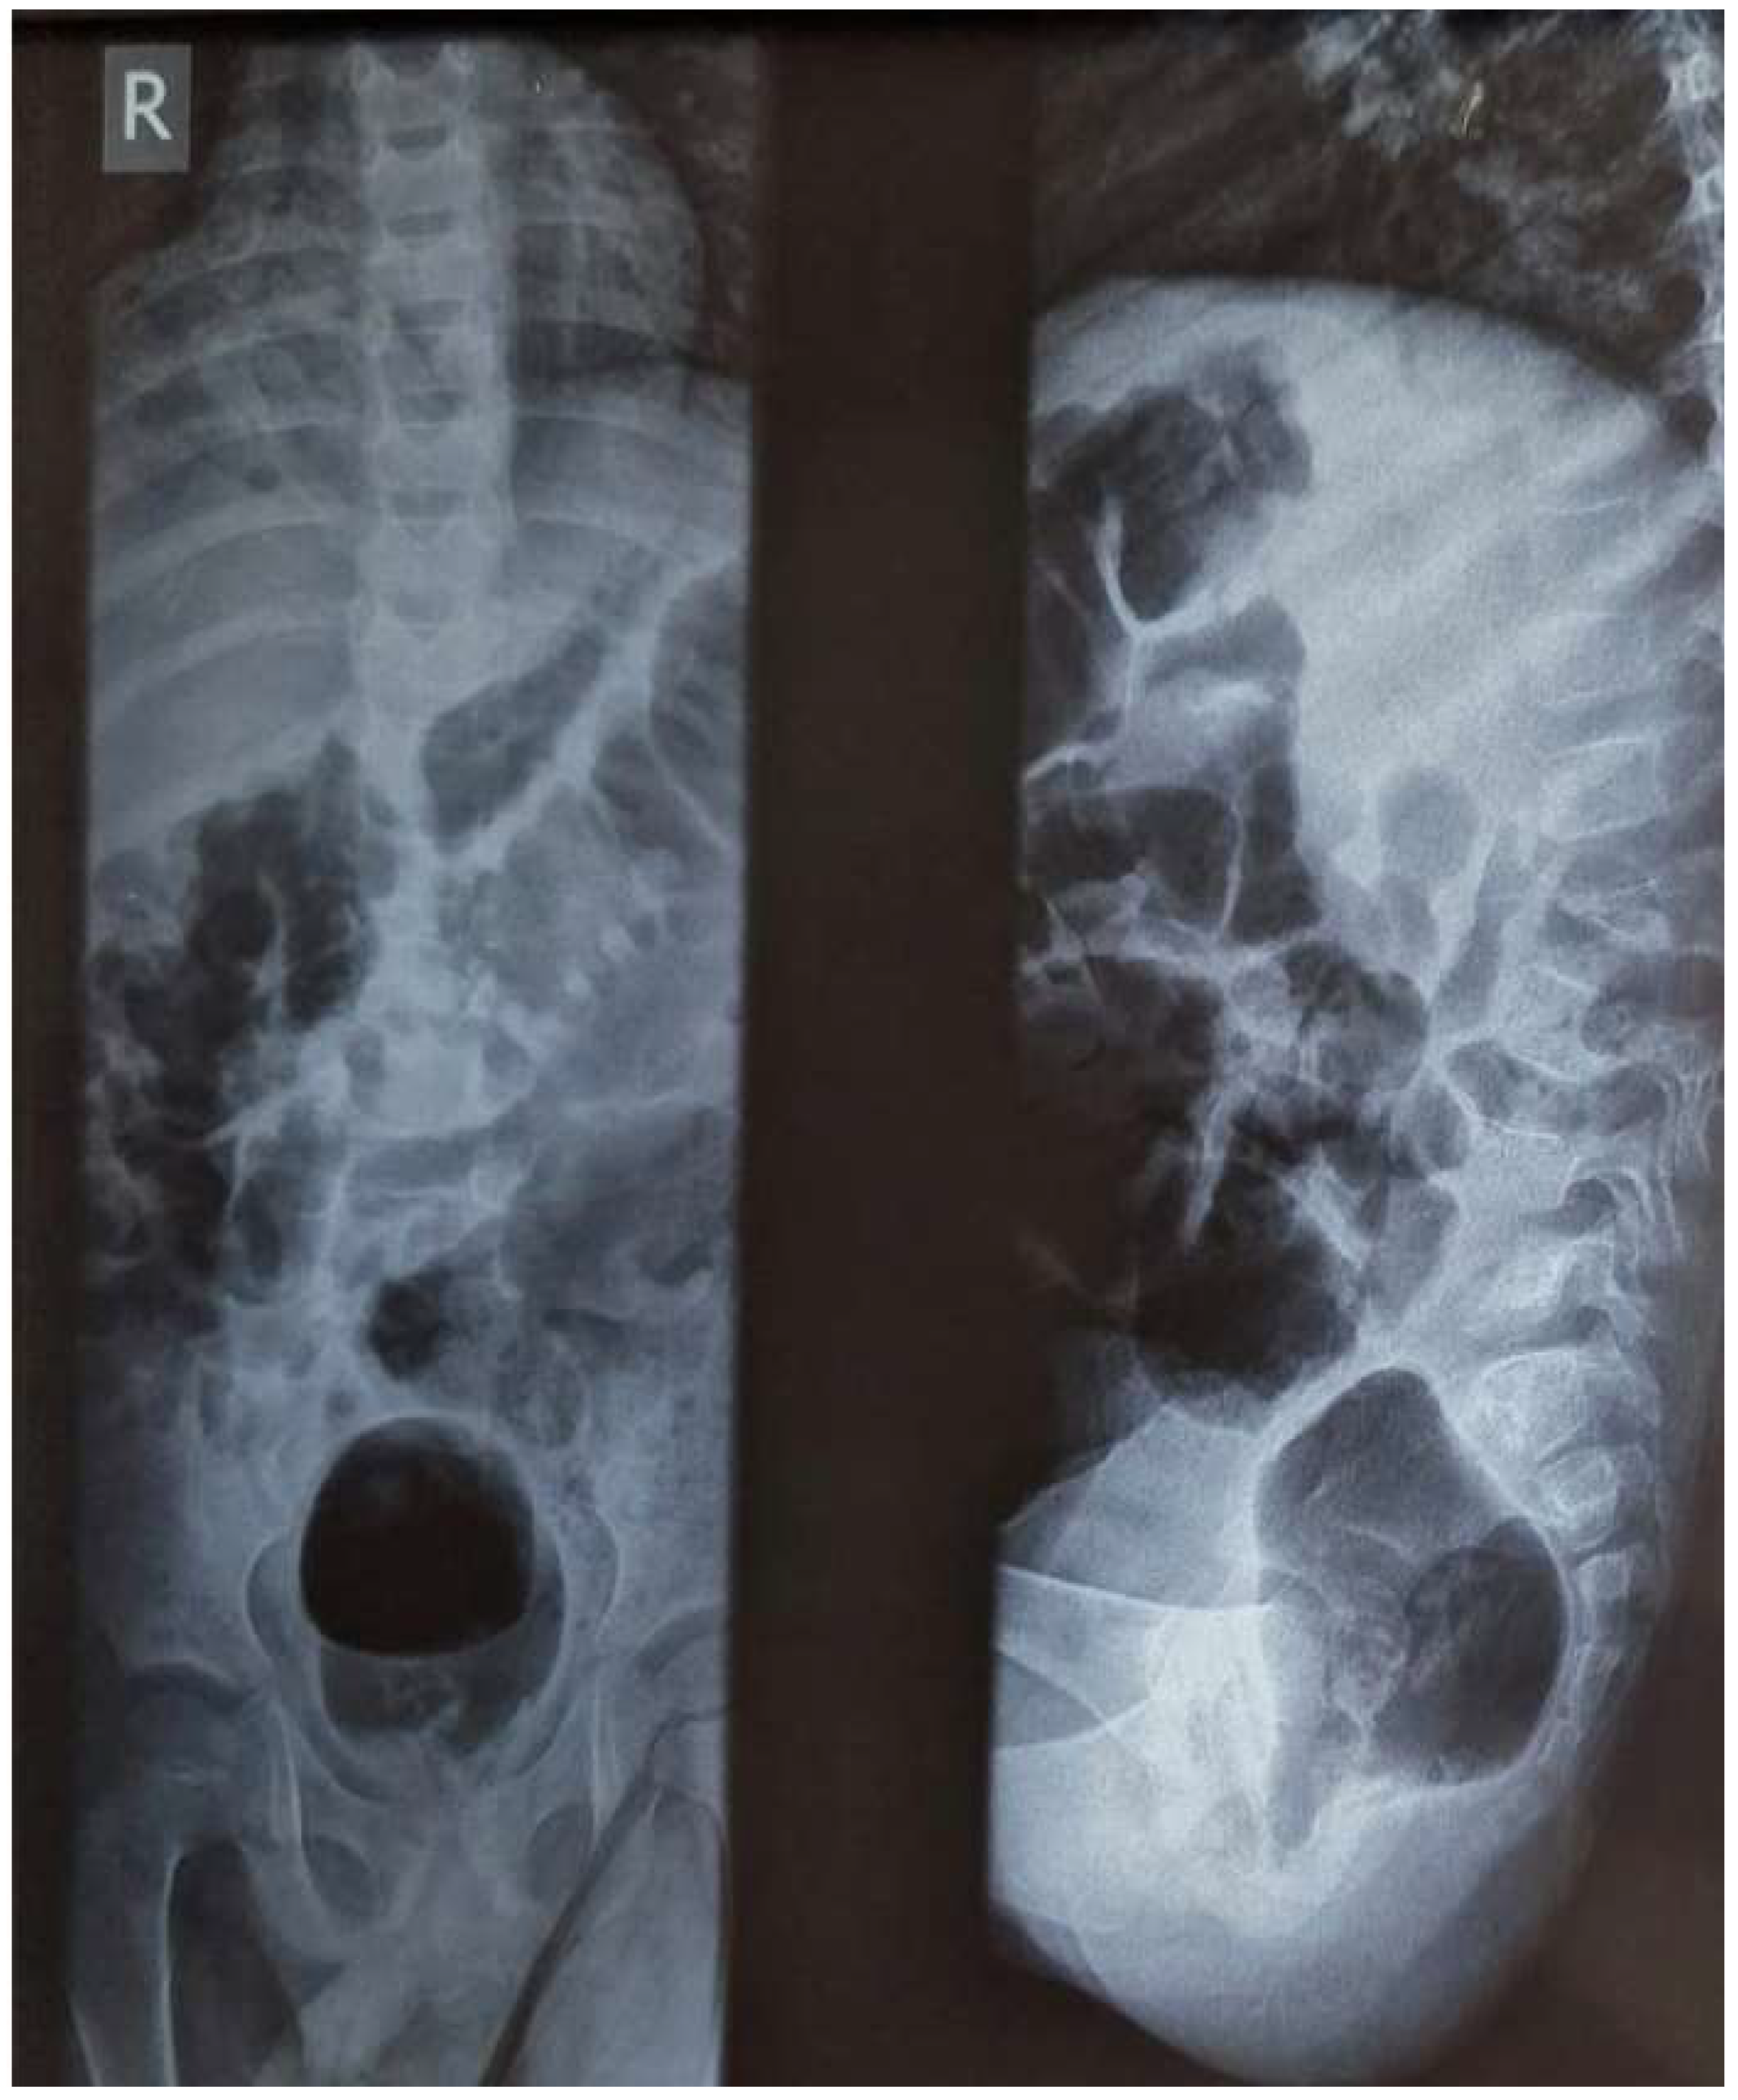

2. Case Report